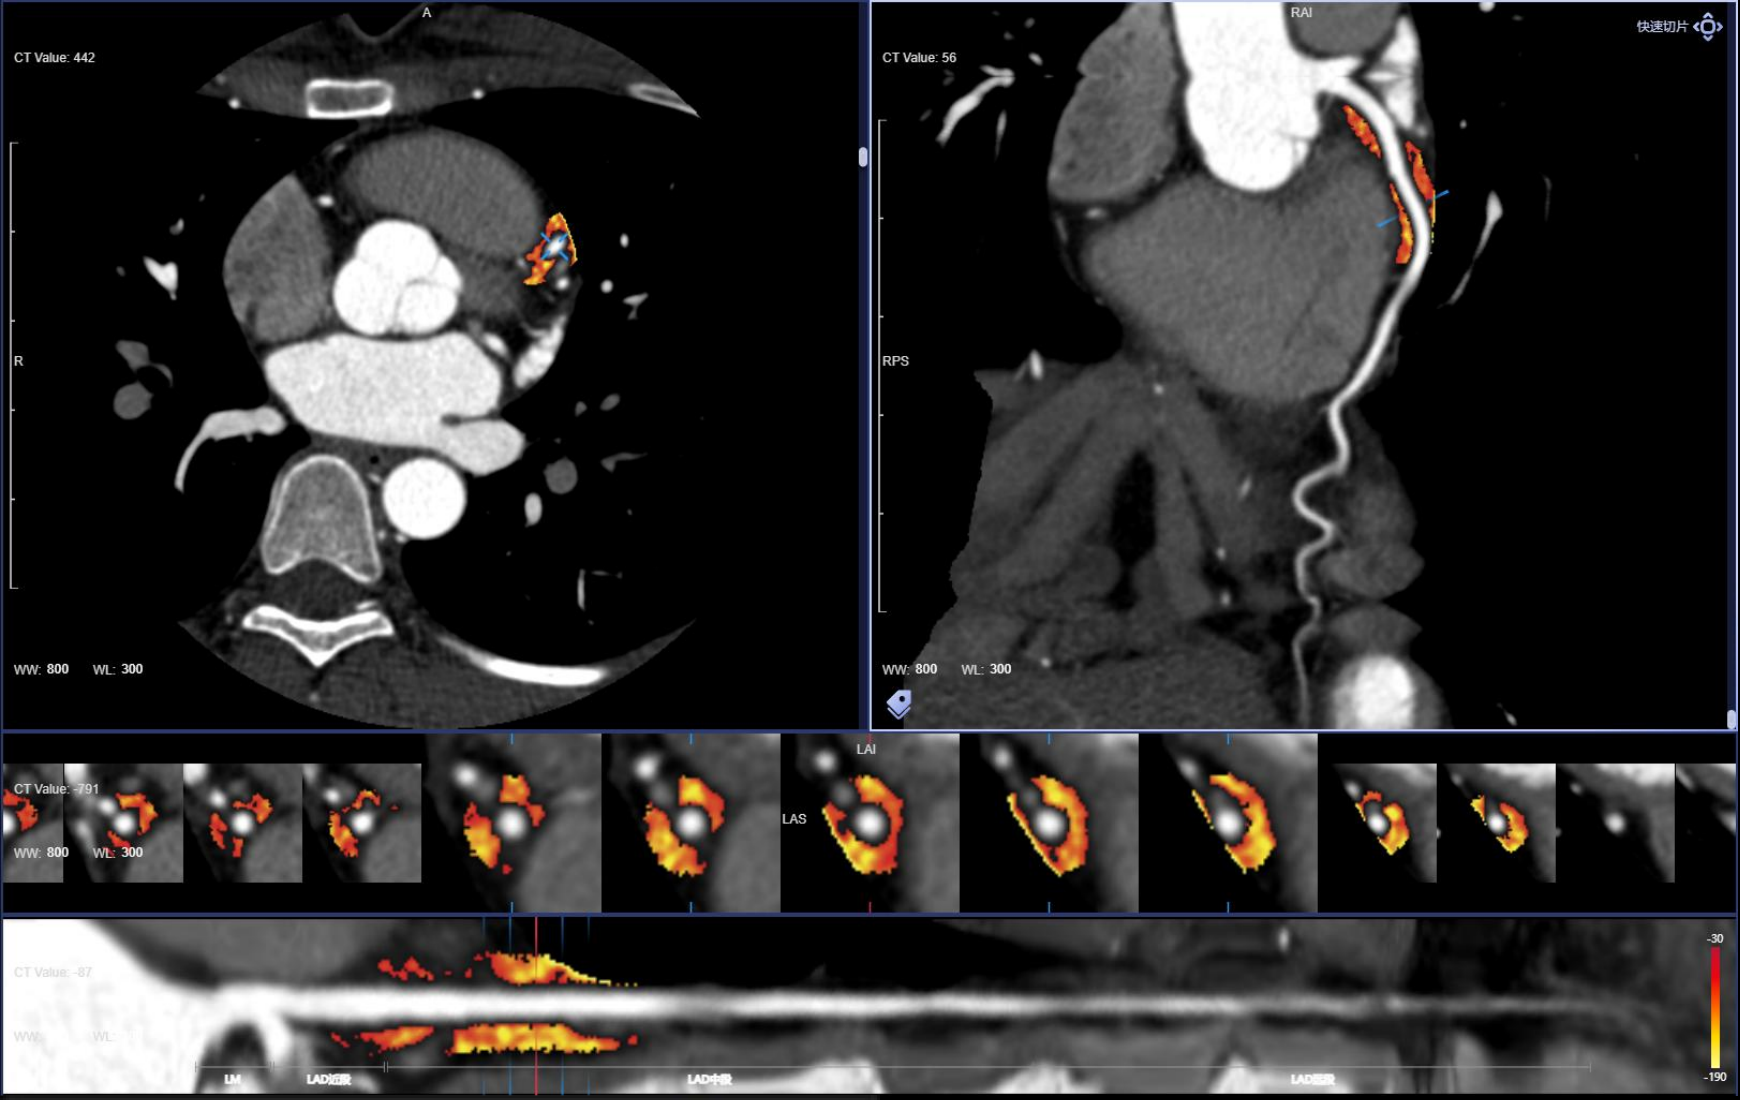

Hệ thống CT tiên tiến này sở hữu tốc độ quay siêu nhanh 0,286 giây, bóng tia X công suất 7,5 MHU (hiệu dụng lên đến 27,1 MHU) cùng detector độ rộng 40 mm. Nhờ các công nghệ hiện đại, hiệu suất chụp tim vượt trội được nâng lên một chuẩn mực mới, mang lại hình ảnh tim mạch chính xác và ổn định. Thiết bị tích hợp nền tảng AI toàn diện, bao phủ toàn bộ quy trình từ định vị bệnh nhân, quét, kiểm soát liều, giảm nhiễu và triệt tiêu artefact đến hậu xử lý hình ảnh và hỗ trợ chẩn đoán, đảm bảo độ chính xác vượt trội ngay cả trong những tình huống lâm sàng phức tạp nhất.